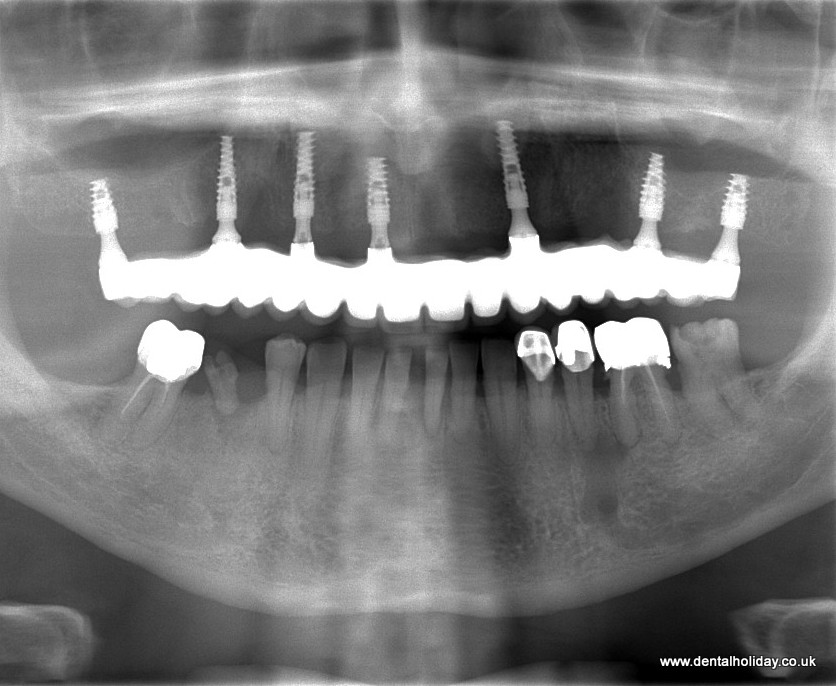

Malcom felt he received fantastic dental treatment abroad at Smile Clinic – Dental Holiday. Malcom, had dentures before his full upper bridge fitted over 7 dental implants.

We are so happy to help many of our UK patients with dentures find the smile they’ve always wanted without the mess and overall in effective dentures.

With implants you will never have to worry that they will slip when you smile or eat! However, we know that implants in the UK are very expensive. At Smile Clinic – Dental Holiday we provide a free consultation with x-rays and treatment plan complete with all the costs that are normally 50-70% less than in the UK.